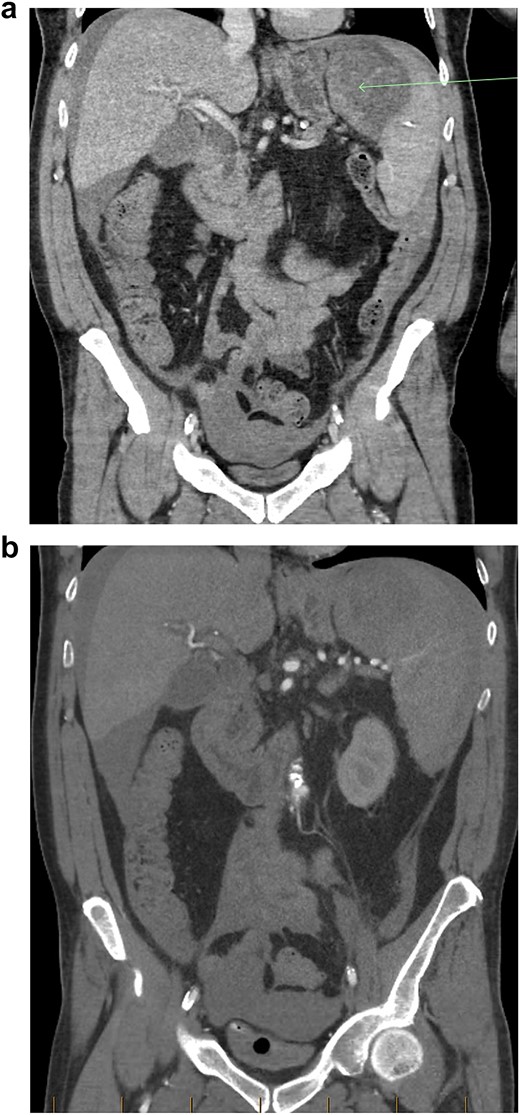

(a) Coronal view of CT-abdomen/pelvis in the portal venous phase showing moderate volume free-fluid/blood around the liver, both paracolic gutters, extending to the lower abdomen and pelvis. There is a large haematoma seen within or adjacent to the spleen (arrow). (b) Coronal view of CT-abdomen/pelvis angiogram redemonstrating the known splenic haematoma, however there was no evidence of active arterial contrast extravasation.